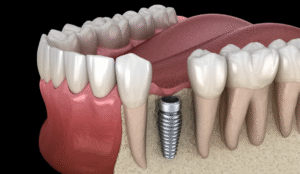

Dental Implants Without Fake Gums: Get That Natural Smile You’ve Always Wanted

So you’re thinking about getting a dental implant. But here’s the thing—you’re worried it’s gonna look fake, right? Like those obvious artificial gums you see...